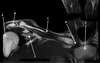

TRICEPS MUSCLE

TRICEPS TENDON

FATTY TISSUE

OLECRANON

MEDIAL EPICONDYLE

ULNA

LATERAL EPICONDYLE

HUMERUS

COMMON FLEXOR TENDON

RADIAL TUBEROSITY

RADIAL HEAD

ANCONEUS MUSCLE

TRICEPS

CORONOID PROCESS

TROCHLEA

BRACHIALIS